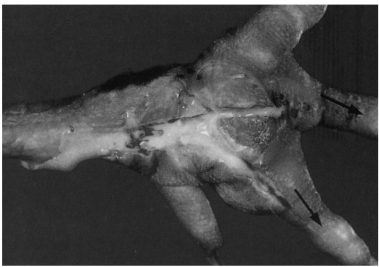

2.关节型痛风 仅在关节的软骨、关节周围组织、腱鞘、韧带等处有白色尿酸盐沉积(图4.1),尤其是趾关节。有些关节面发生糜烂和关节囊坏死,有的呈结石样的沉积,称为痛风石(瘤)。

图4.1 家禽痛风关节沉积尿酸盐